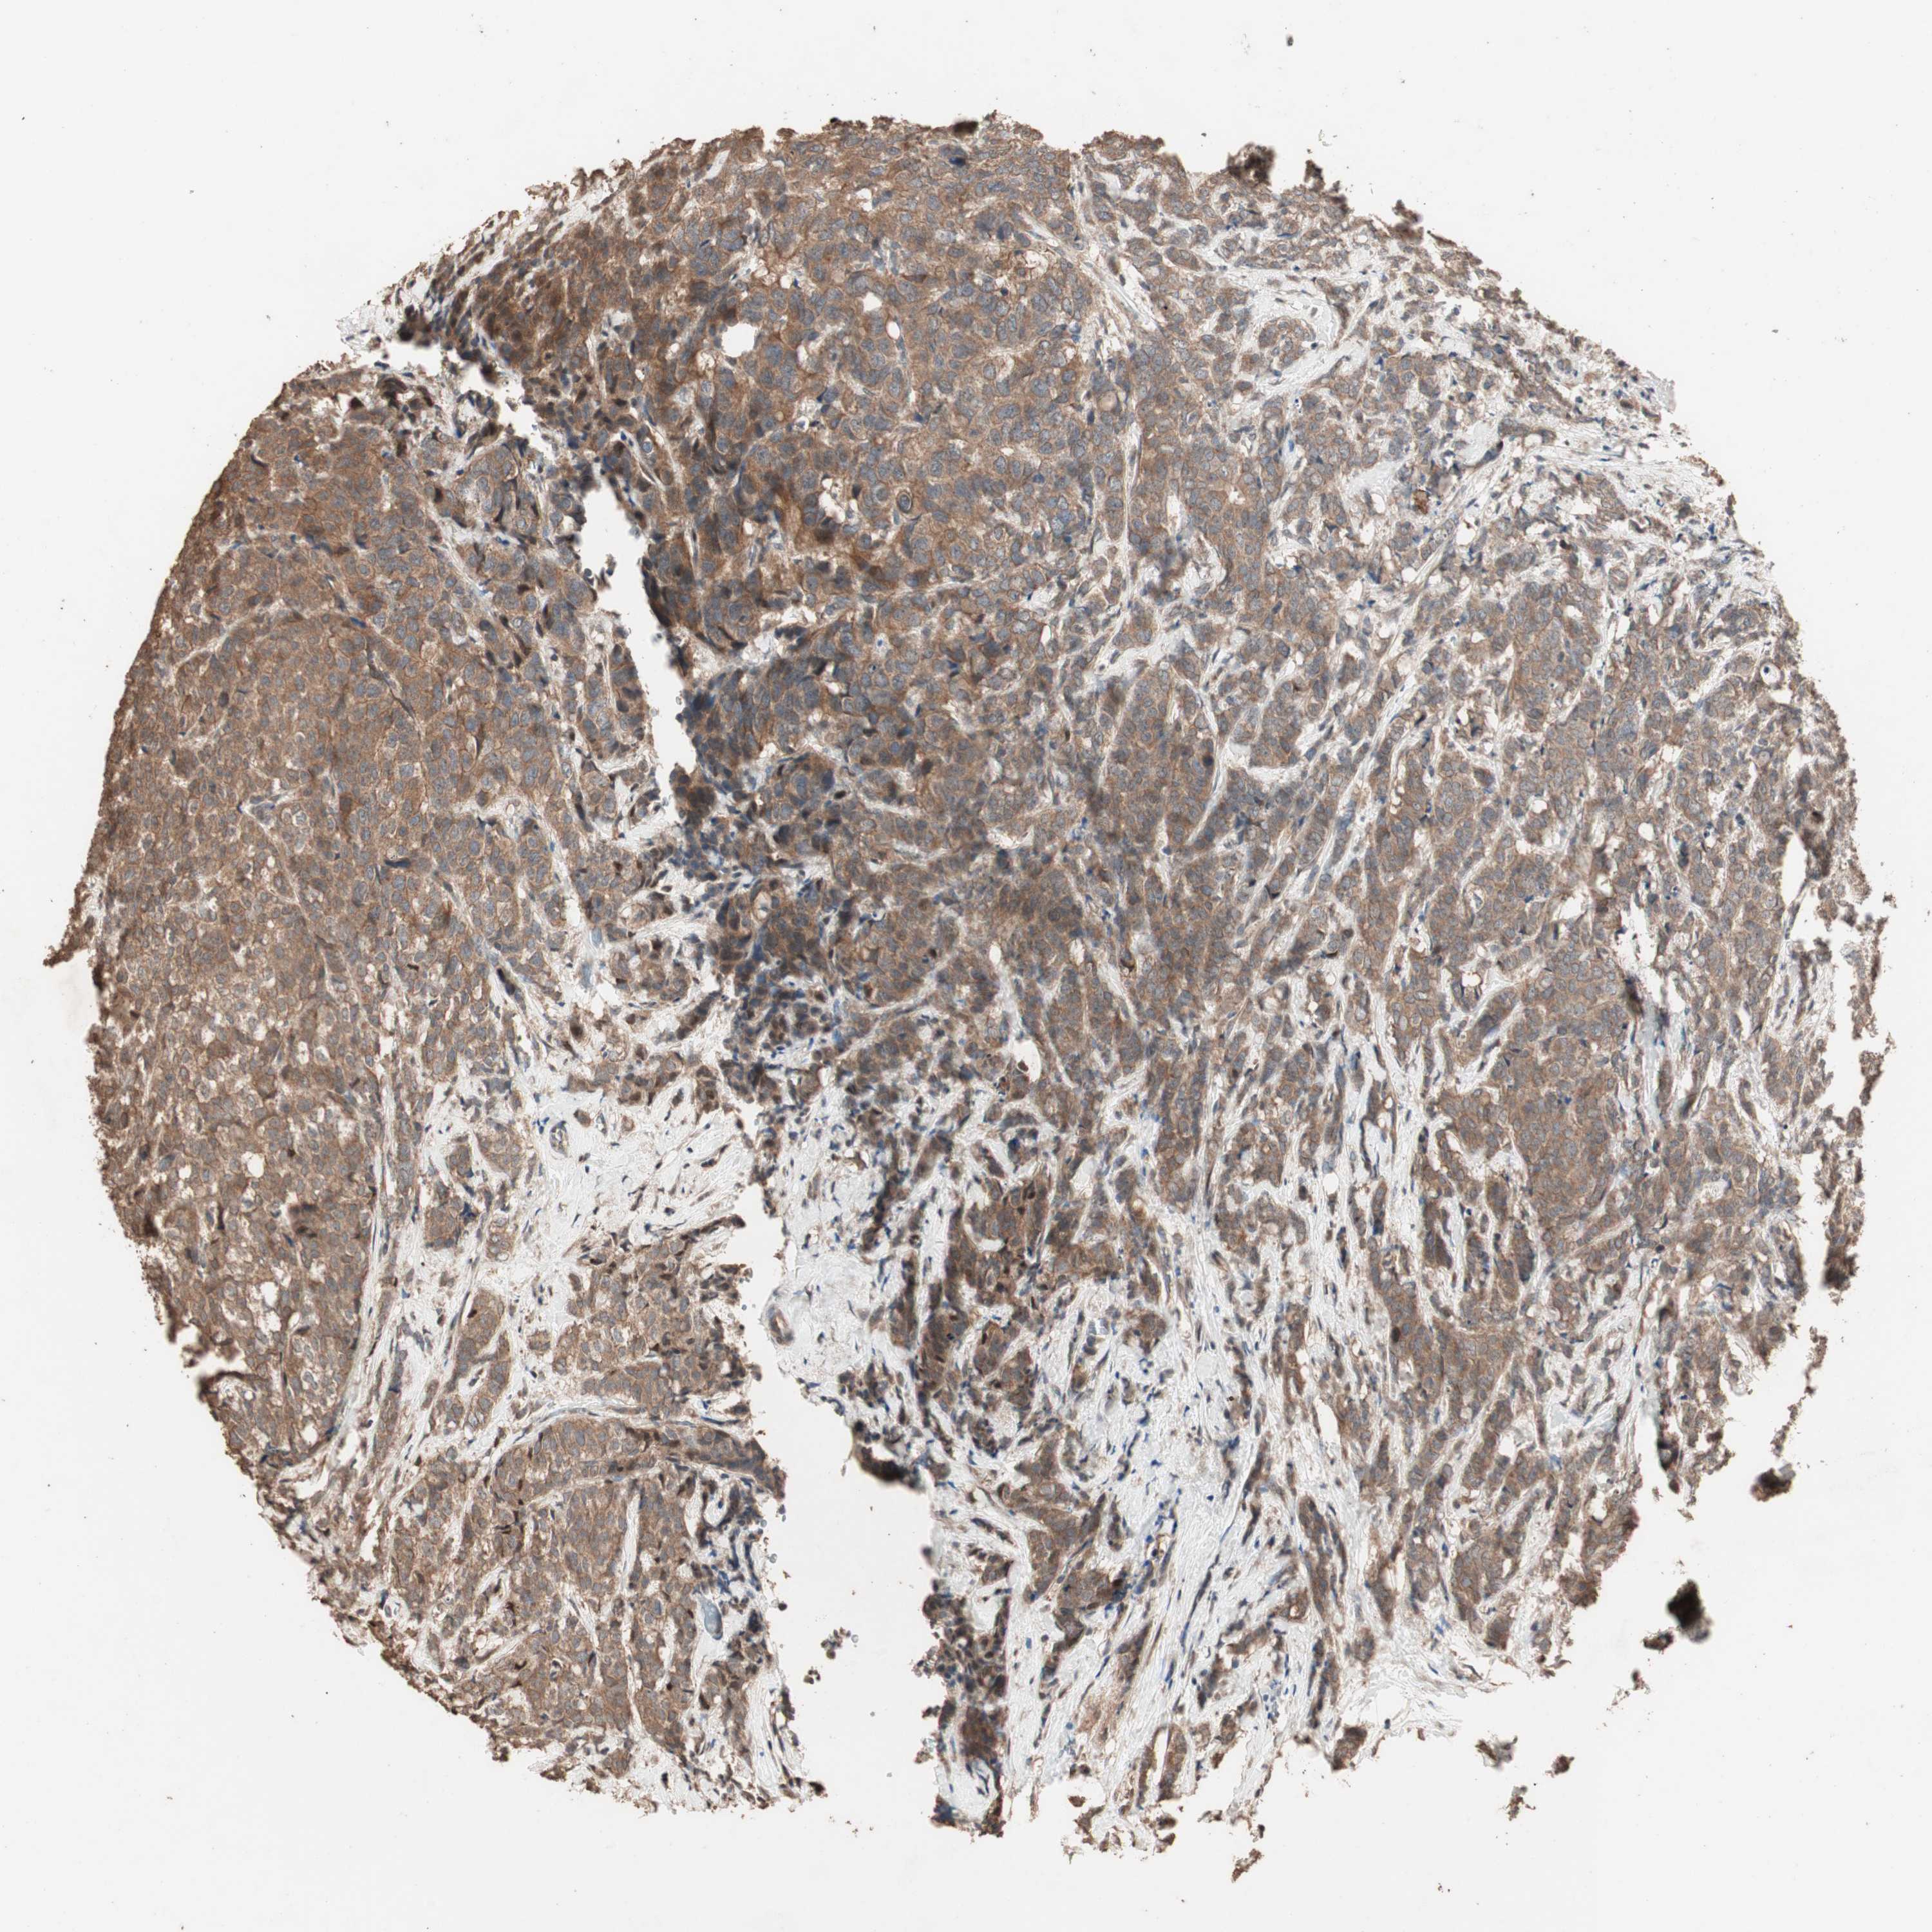

CANCER BREAST CANCER Show tissue menu

BRCA TCGA BRCA VALIDATION PROTEIN EXPRESSION